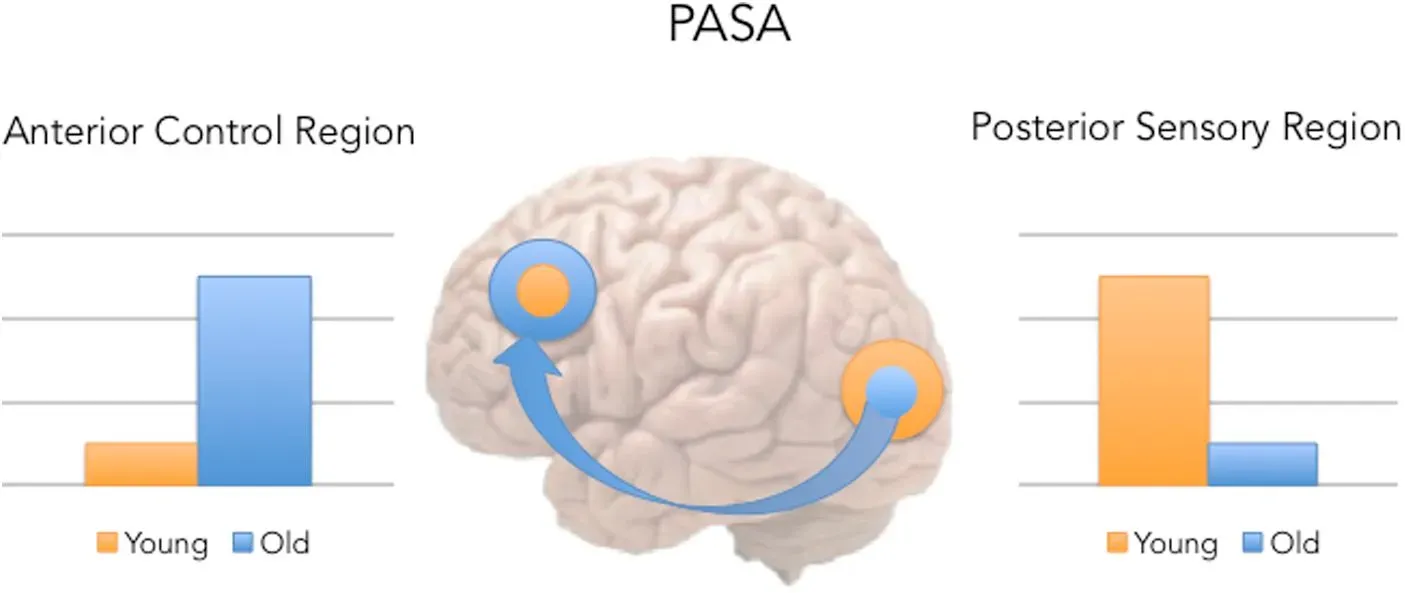

When neuroscientists looked closer, they saw that aging brains could sprout new connections between neurons, strengthen existing pathways, and recruit fresh regions to handle demanding tasks. In one sense, the older brain behaved like a city that has lost a major bridge but reroutes traffic through side streets and newly built overpasses. The routes may be different from those in youth, but they can still get you where you need to go. That flexibility is the essence of neuroplasticity, and it does not suddenly switch off at age forty, sixty, or even eighty.

Modern imaging techniques, from high‑resolution MRI to tools that track blood flow and electrical activity, flipped that old script. Again and again, researchers saw adult brains reorganize after stroke, injury, or intense training, sometimes in as little as a few weeks of practice. Experiments in which adults learned to juggle, navigate complex virtual cities, or take up musical training late in life all showed structural and functional changes in key brain regions. Instead of a finished statue, the brain started looking more like a clay model that stiffens with age but can still be reshaped with enough consistent pressure.